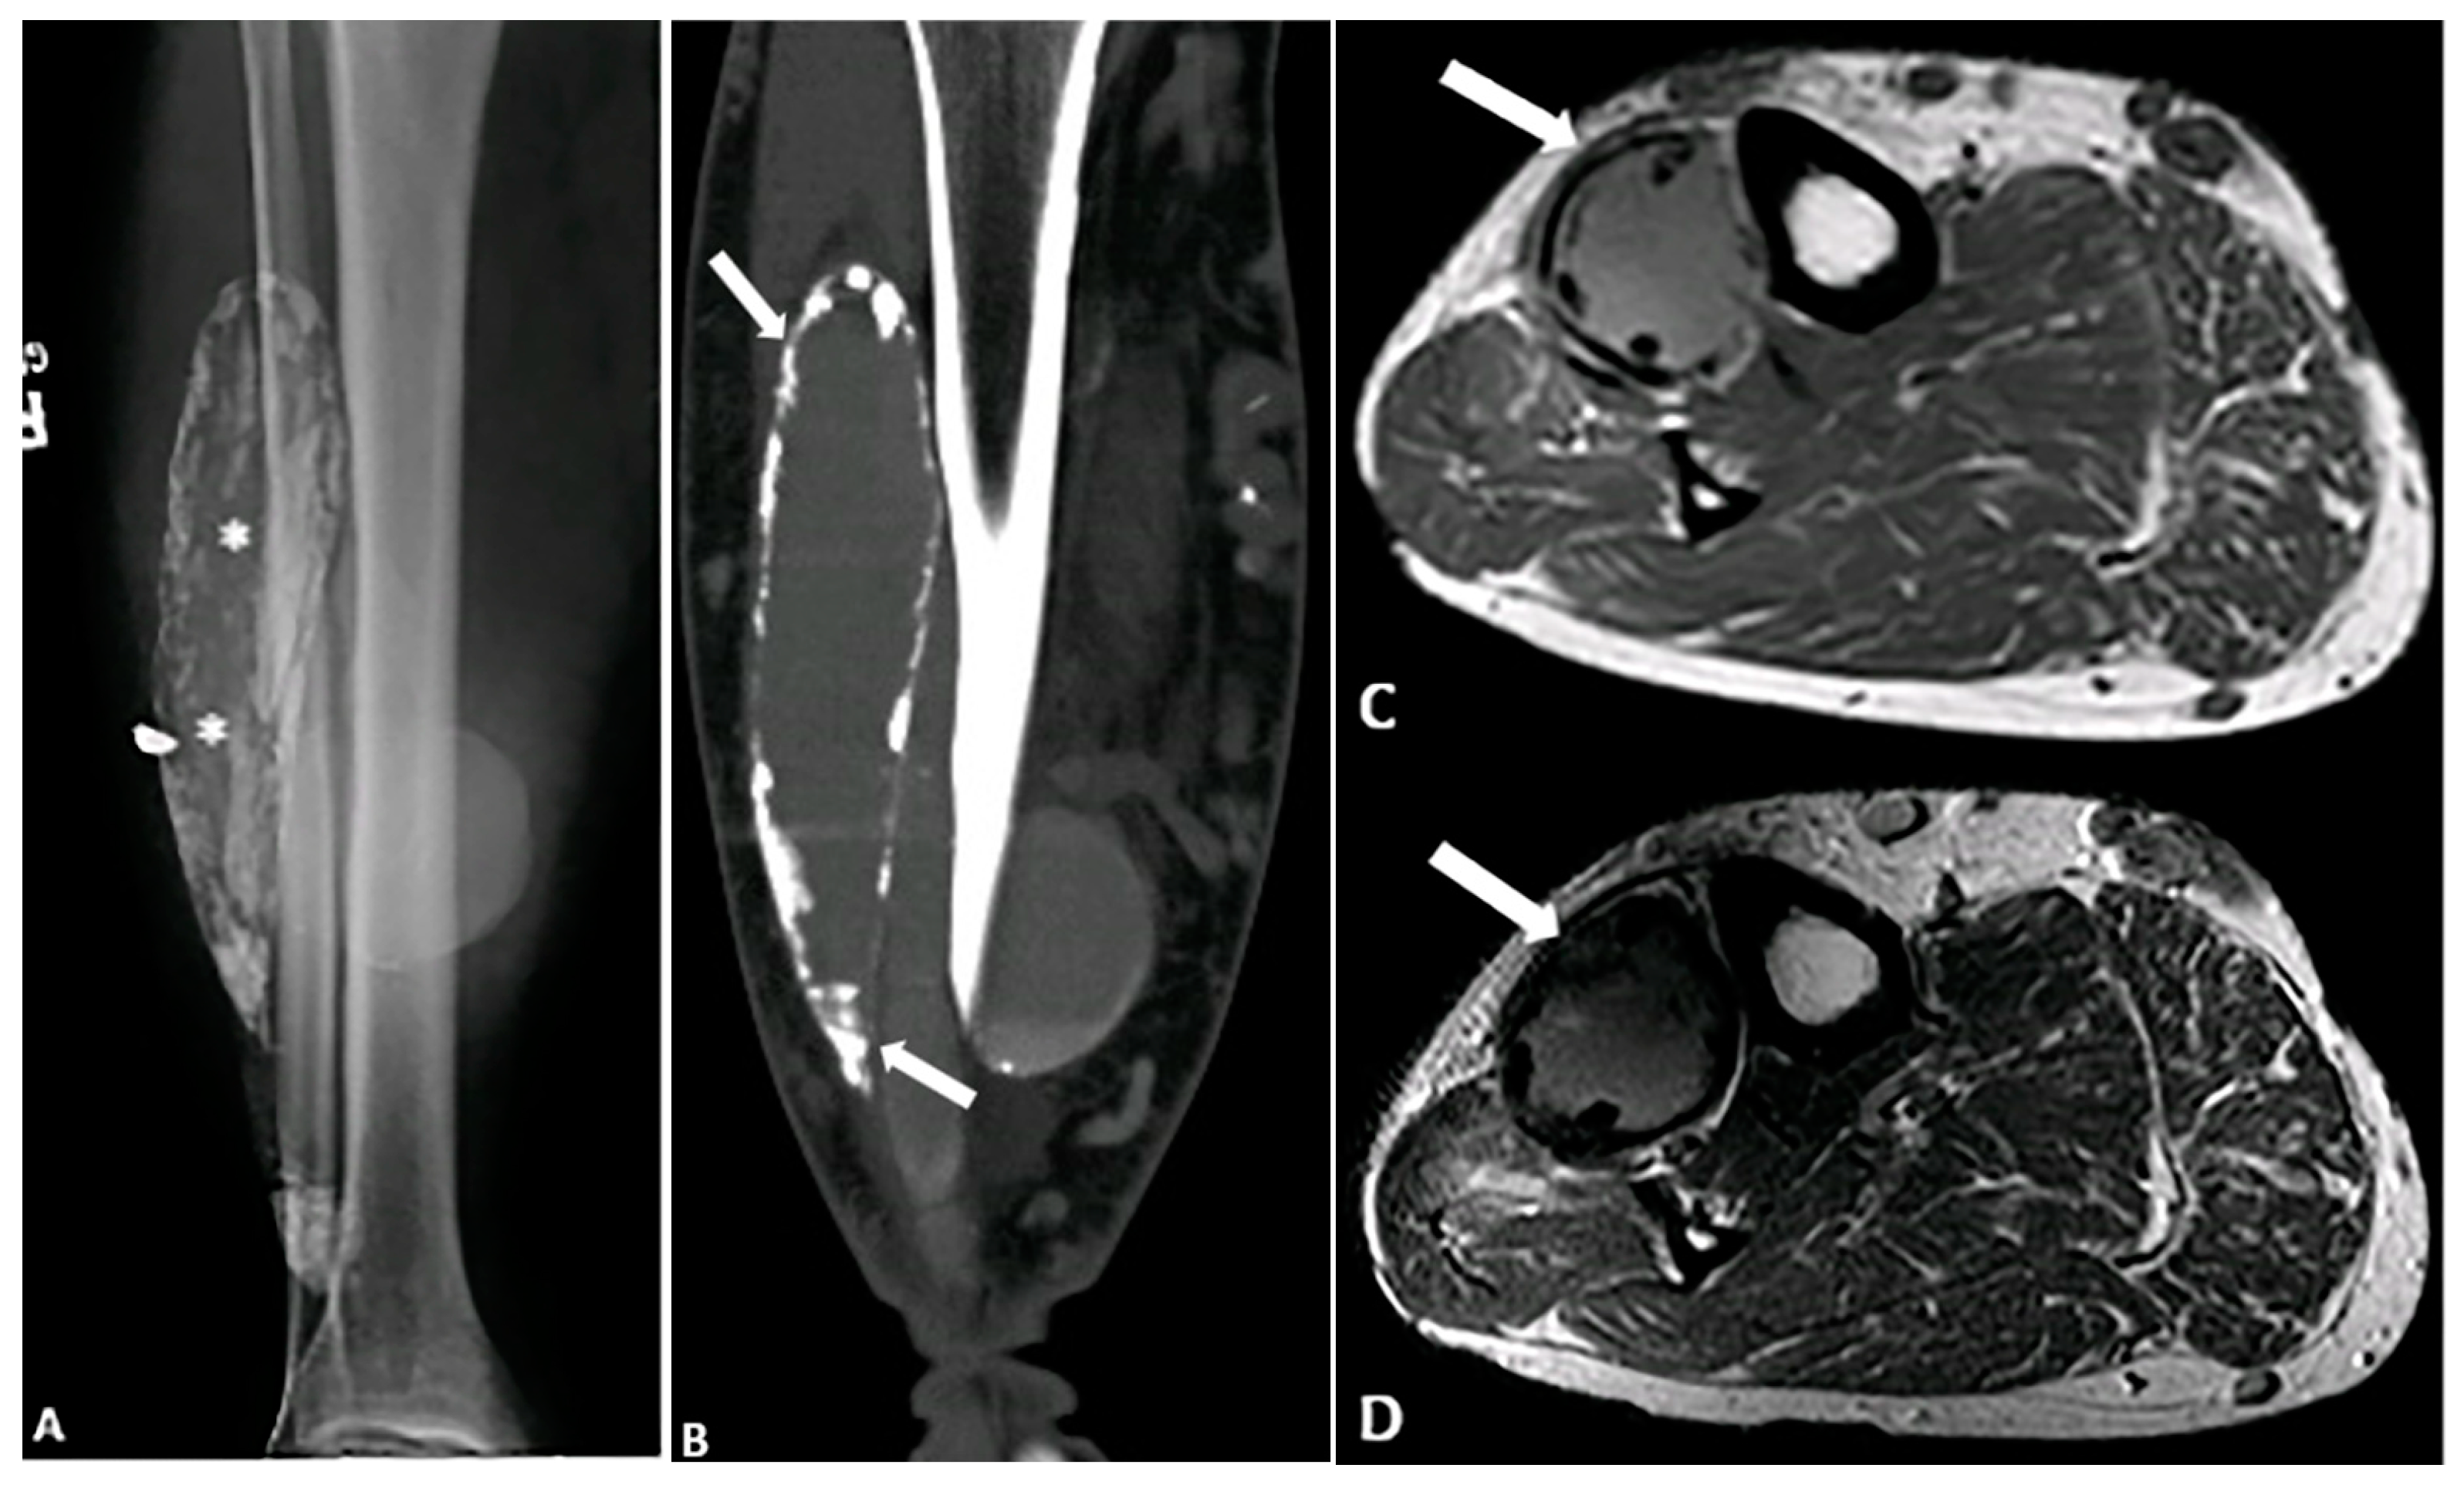

5.5. Calcific Myonecrosis

- O’Dwyer, H.M.; Al-Nakshabandi, N.A.; Al-Muzahmi, K.; Ryan, A.; O’Connell, J.X.; Munk, P.L. Calcific myonecrosis: Keys to recognition and management. Am. J. Roentgenol. 2006, 187, W67–W76. [Google Scholar] [CrossRef]